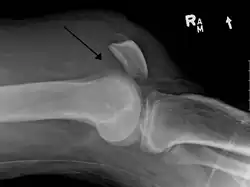

Quadriceps tendon rupture in plain X-ray -

Quadriceps tendon rupture in plain X-ray: Incomplete rupture with haematoma in tendon. -